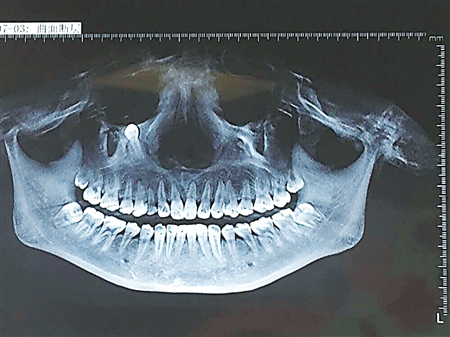

2日,曹芳在当地医院拍了牙部CT,从片子上可以清晰看到,她的右眼眶下有一个状如锥子的物体,医生告诉她这是埋伏牙。“所谓埋伏牙,即牙齿萌出期已过而仍在颌骨组织中未能萌出的牙齿。简单点说,就是你的乳牙迟迟不掉,导致恒牙没地方萌出,只能在颌骨内游走,成了一颗隐患牙。”当地医生告诉她,这颗埋伏牙若继续往上移,会造成眼部肿胀,甚至有可能戳破眼球。但医生同时表示,手术风险较大,他们也没有十足把握,这让曹芳很犹豫。

8日,曹芳从广州回到了广安,在邻居的推荐下,她马不停蹄地来到第三军医大学大坪医院求助。该院颌面头颈外科主治医师丁琳琳看了曹芳的牙部CT后,决定通过手术拔除这颗埋伏牙。“这牙埋藏在骨肉中,肉眼根本无法直视,加之它紧挨鼻腔粘膜,拔除时稍一用力,牙也许会掉入鼻腔内,给患者造成更大创伤。”

丁琳琳介绍,后来通过反复研究CT,他们制定出一套完备的手术方案。昨日,这颗长约3厘米的埋伏牙终于被顺利拔除。